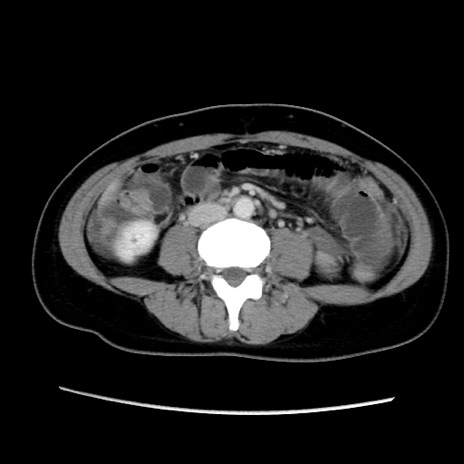

MRI(4日後)

【症例】40歳代女性

【主訴】上下腹部痛

【現病歴】2日目から下腹部痛あり。夜間は痛みで眠れなかった。昨日より上腹部痛と下痢が出現。臥位で痛みは軽快したため、休んでいた。本日になって臥位でも立位でも痛みが強くなってきたため救急要請。

【既往歴】子宮内膜症

【身体所見】部:平坦・軟、左上下腹部に圧痛あり、反跳痛あり。

【データ】WBC 21800、CRP 26.78